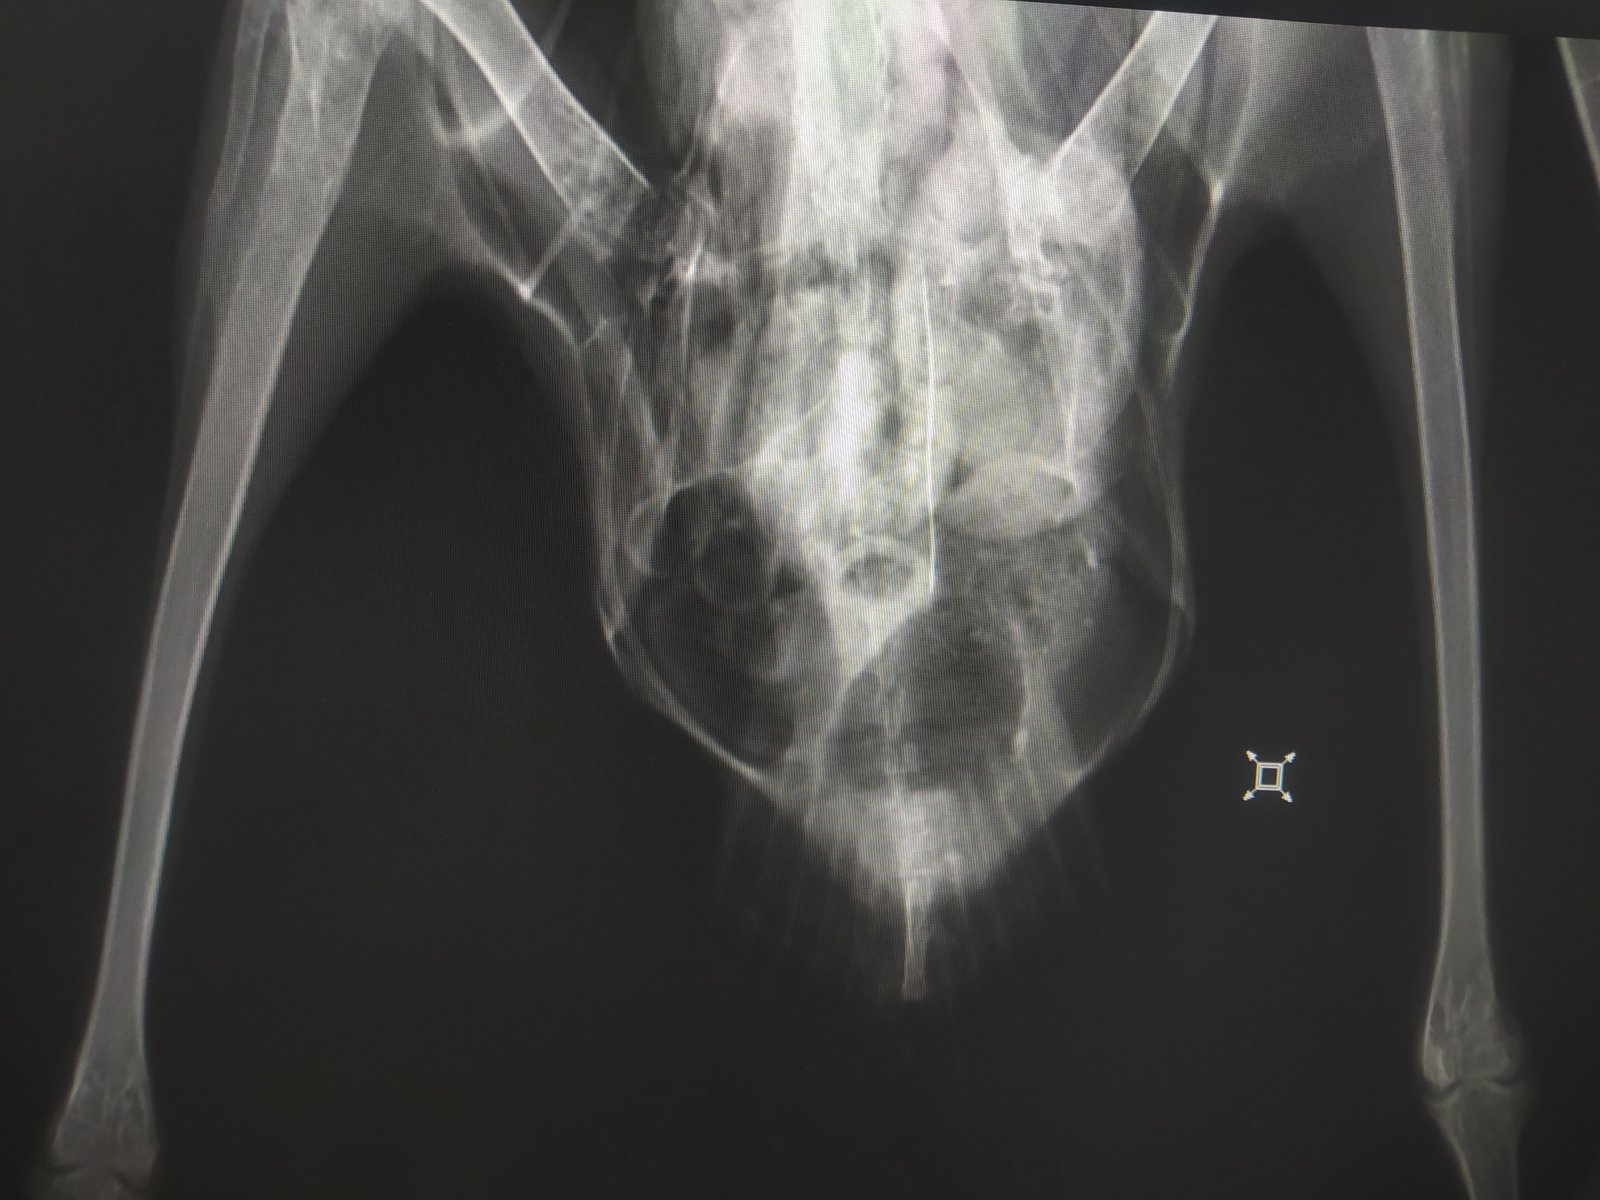

Четрые дня назад на участке нашла птицу, убегает, клюется, самостоятельно ест и пьет. В первый день была покормлена 2 варёными яйцами, все остальные дни только размороженная рыба. Днём гуляет по участку, на ночь убираю в картонную коробку. Думаю это серебристая или средиземноморская чайка. Вес около двух кг. На рентгене переломов не замечено

Короче, с костями птицы все было нормально, оба крыла рабочие, но.. Вот эта вот крохотная металлическая проволока проигнорированная мной на рентгене как артефакт её и убила(

Распорот кишечник, гнойный перетонит, тромб в сердце (скорее всего посмертный)